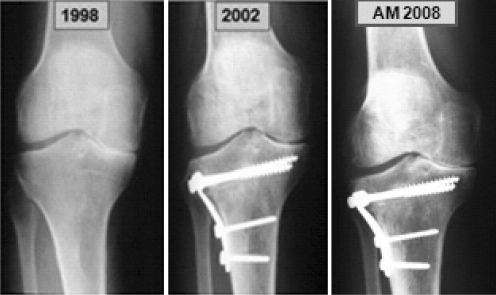

Radiologically, the realignment with joint space widening was sufficient to delay progression of the arthritis or to manage it. Nonetheless, reasonable improvement and stabilisation with few complication is observed on the evolution of osteoarthritis after nearly ten years. It is worth noting that, even though the radiological degenerative changes may evolve in eventual aggravation, the clinical symptoms generally continue to improve after the intervention (Fig. 4).

Fig. 4.

A 63-year-old man (A.M.) who had a painful arthritic right knee following a malalignment of the tibial diaphysis. After high tibial closing osteotomy and over a period of several years, he could walk and run without pain. The last two years he is a bit less satisfied due to mild pain. However, the patient is satisfied enough to not request an arthroplasty even after recurrence of medial space narrowing at the final follow-up

Therefore, the approximate five degrees of valgus, desired and achieved by the osteotomy, seem to be reasonably effective.